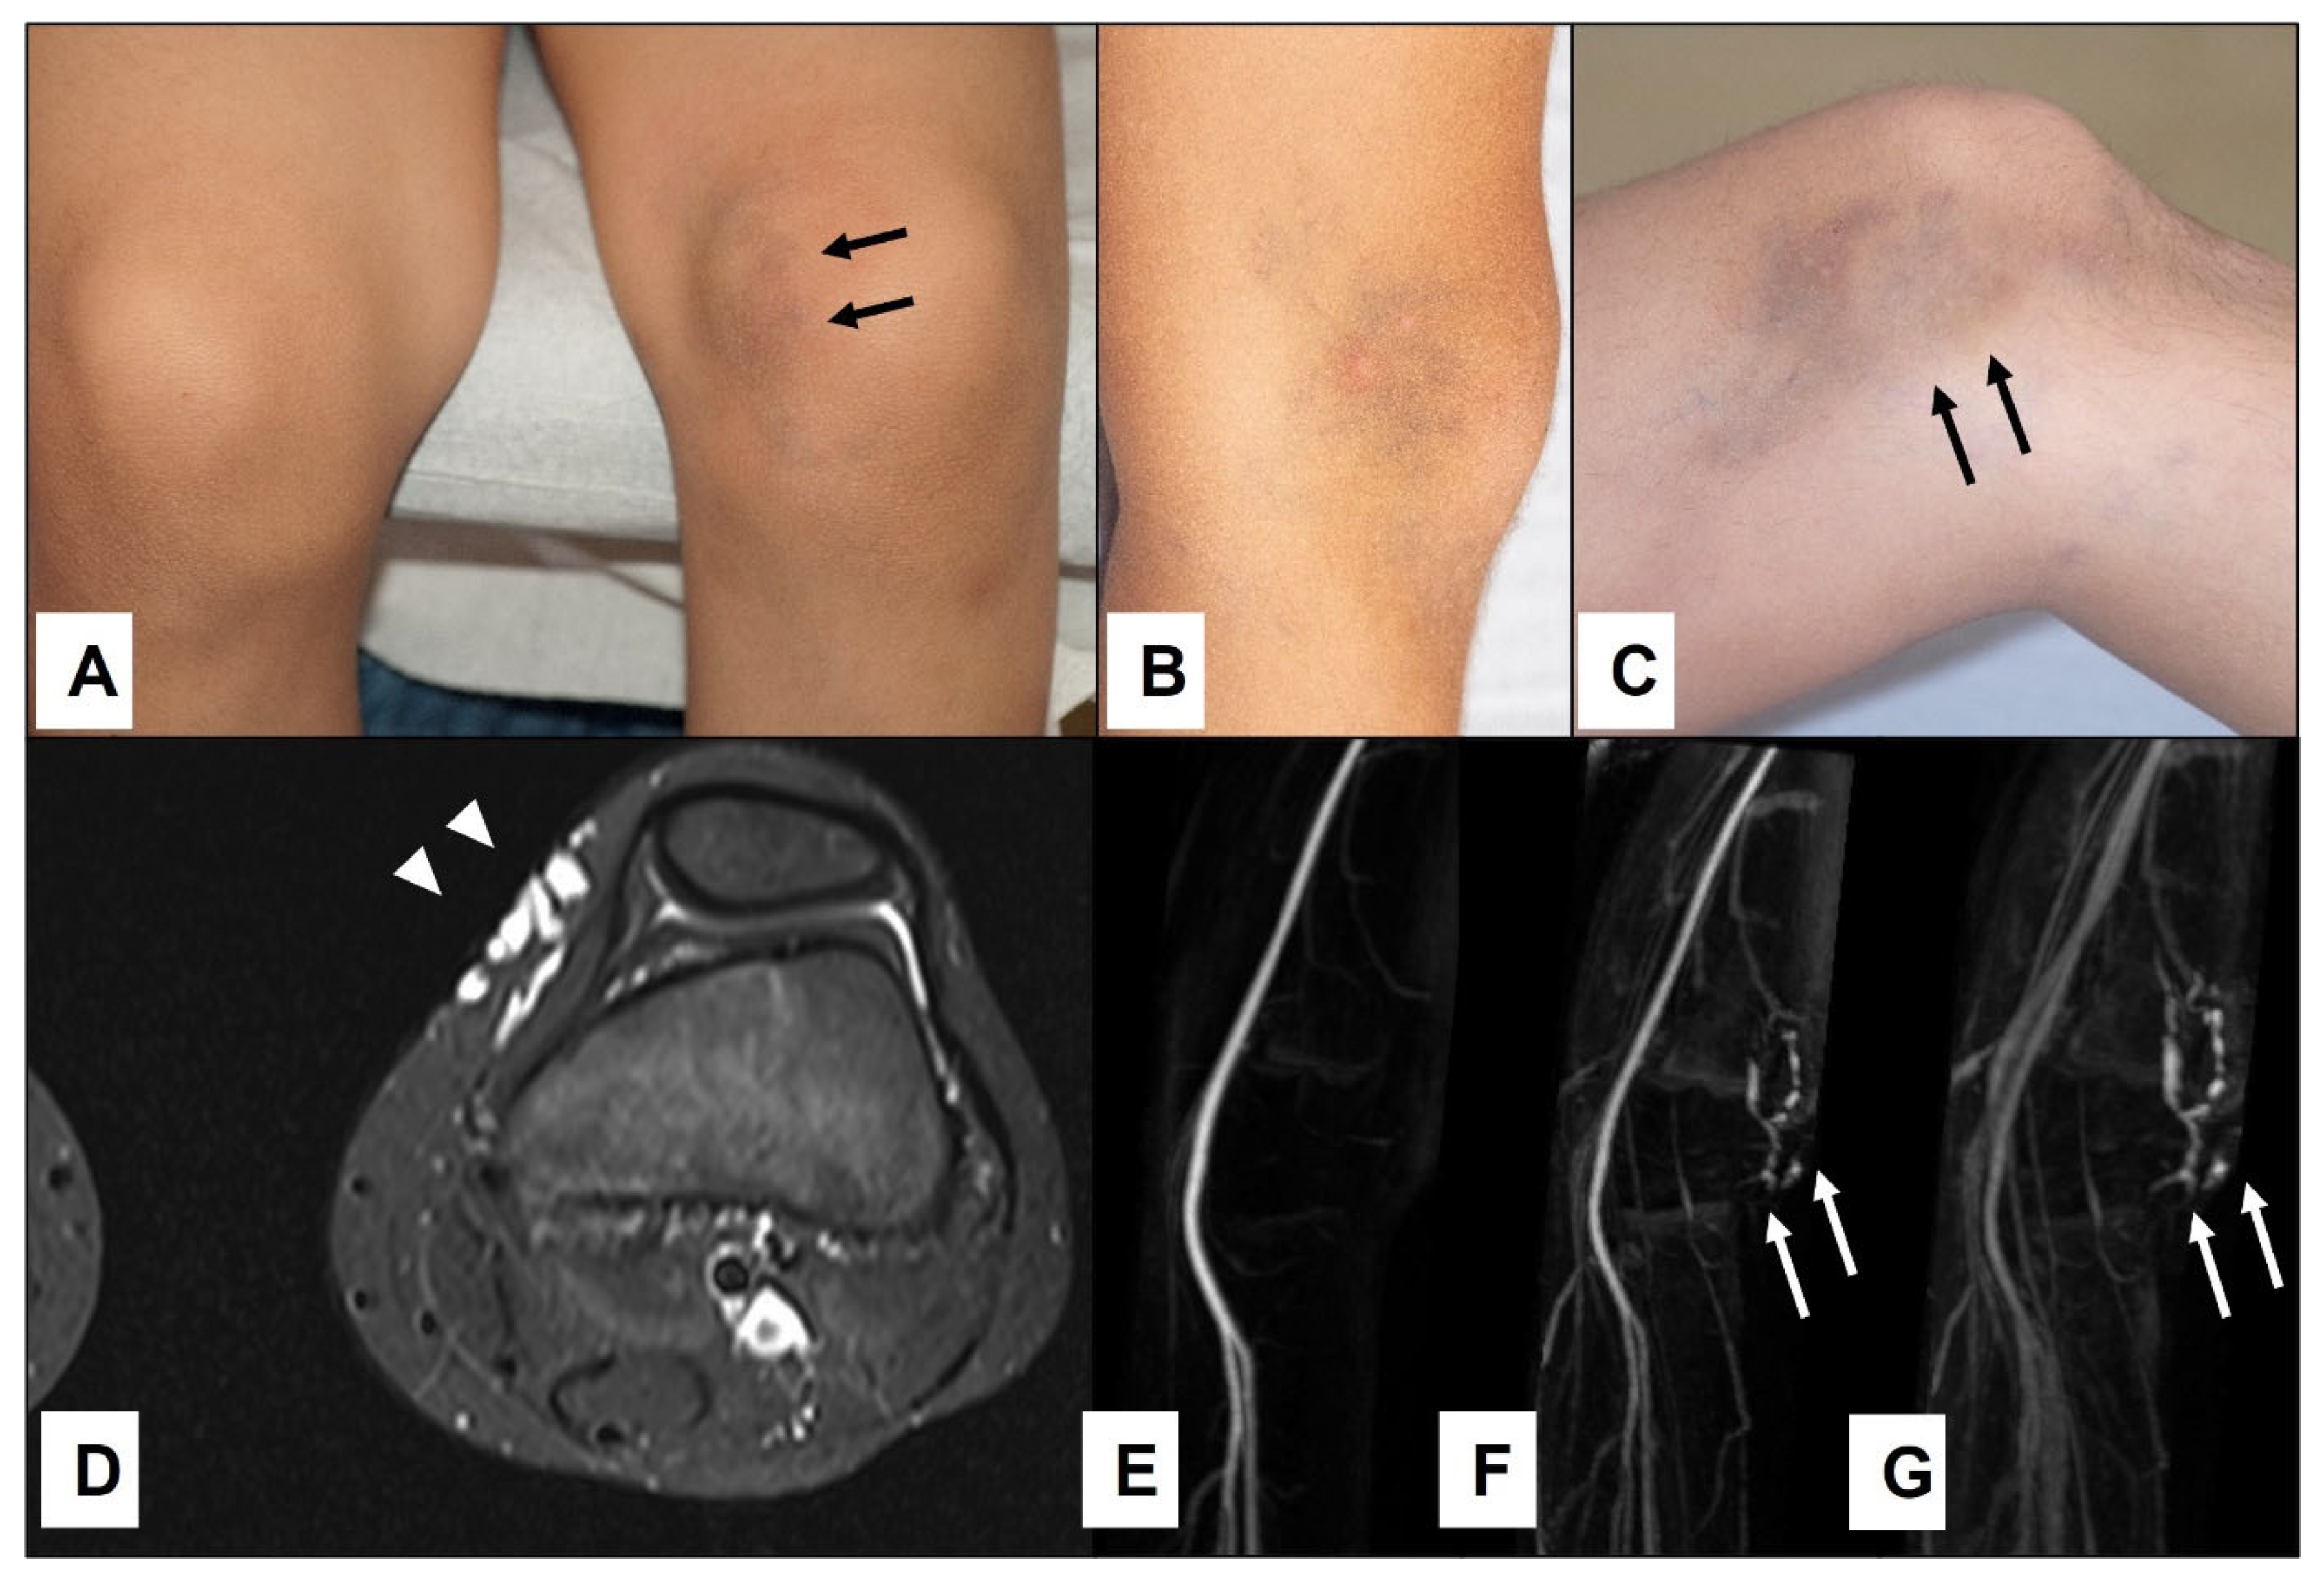

Figure 2.

An 11-year-old boy presented with bluish swelling medially on the left knee (A): white (arrowheads). The lesion was compressible and would drain and flatten with the elevation of the leg indicating clinically the venous malformation (B,C)—(white arrowheads). MRI showed the exact location and extension of tubular-cystic venous malformation (D)—(white arrowheads), which filled with contrast material in the venous phase of the MR angiography (E–G)—(white arrows), confirming the clinical diagnosis. The patient was referred to sclerotherapy.